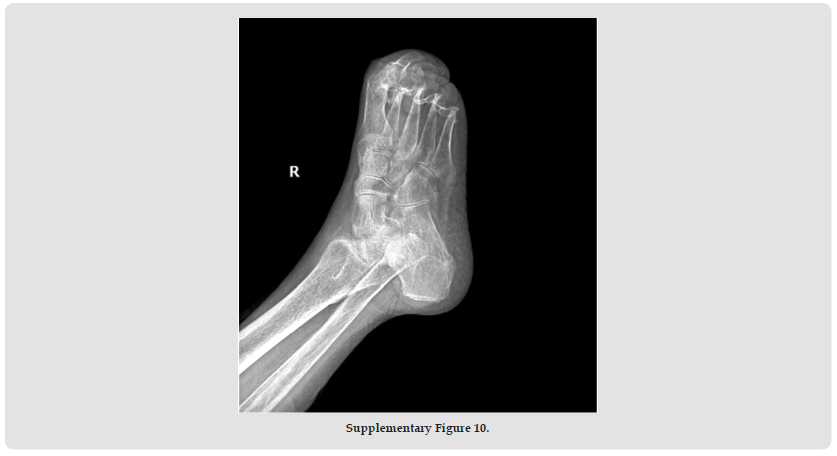

Psoriatic arthritis (PsA), a systemic autoimmune disease, manifests with remarkable clinical heterogeneity [1]. While axial involvement and peripheral joint destruction are well documented, the coexistence of severe spinal kyphosis and Mutilans-type arthropathy remains exceptionally rare. We present a diagnostically challenging case with concurrent progressive spinal deformity and osteolytic features of Mutilans [2]. This case report describes the complex clinical presentation of a rare psoriatic arthritis (PsA) patient with severe kyphosis and mutilating arthritis. A 69-year-old woman with a 50- year history of psoriasis developed worsening skin symptoms and joint pain in 2019. She was treated with cyclosporine, ezicizumab and secukinumab, which resulted in partial relief of skin symptoms but progressive joint destruction. Over the past two years, he had developed a complex sagittal and coronal spinal deformity (thoracolumbar kyphosis with scoliosis), accompanied by characteristic “telescopic” phalangolysis and ulnar deviation of the right hand. His serum markers (RF, anti-CCP, etc.) were normal. Imaging showed the coexistence of heterotopic ossification and osteolysis, consistent with the diagnosis of residual PsA combined with spinal PsA. The clinical significance of this case is that it highlights three key issues. Firstly, rapidly progressive spinal lesions can occur in the absence of a typical serological marker (negative HLA-B27); secondly, biological agents can cause separation of skin and joint effects.

Third, mechanical stress may accelerate the progression of spinal deformity in susceptible individuals. This suggests that dynamic monitoring of the spine in PsA patients should be intensified, especially in patients with long-term good skin control but new axial symptoms, and the evaluation strategy should be adjusted. Future research needs to further explore the mechanical-inflammatory interaction mechanism and establish precise treatment pathways for different clinical phenotypes. This case provides an important clinical demonstration to recognise the heterogeneity of PsA and the complexity of treatment (Supplementary Figures 1-11).